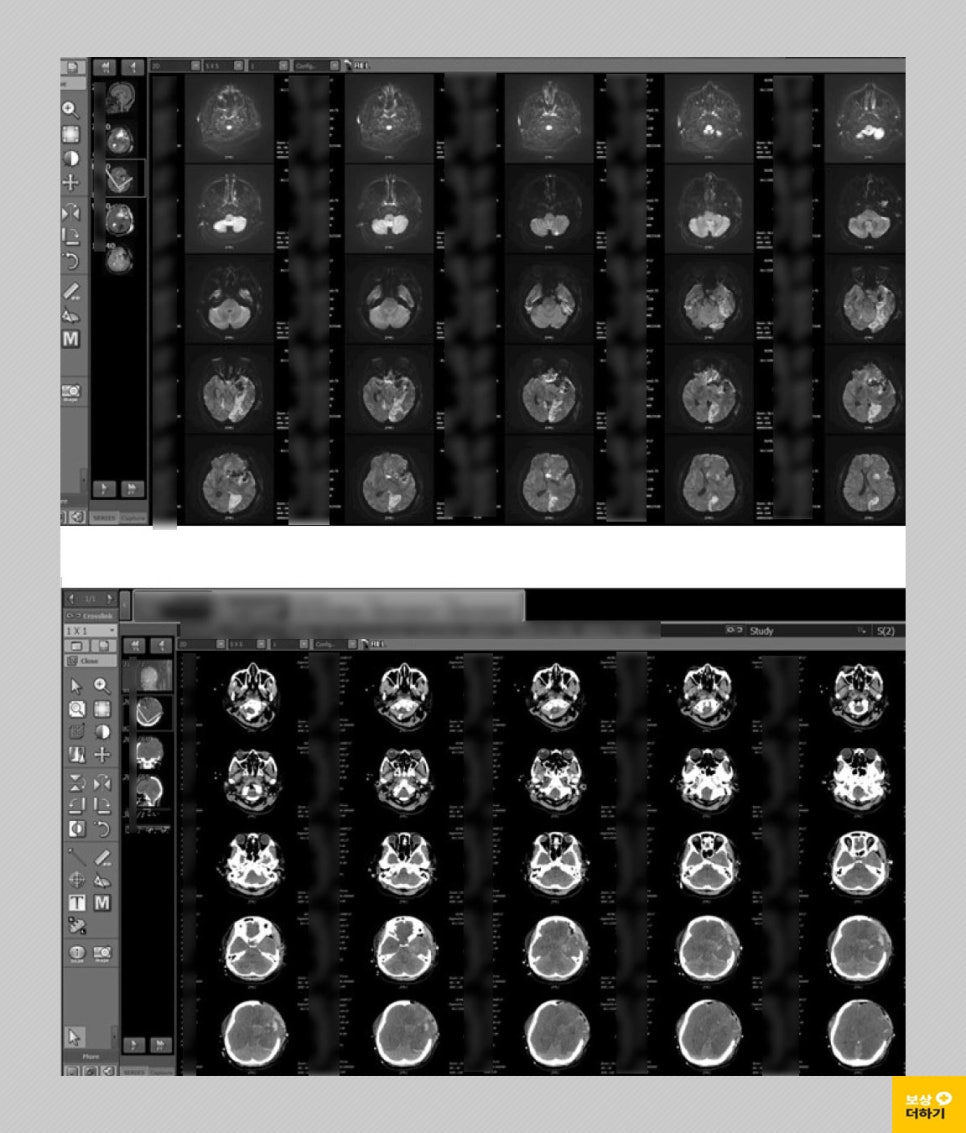

50대 여성이신 박 00 님은 어느 날부터 몸의 불편함을 느끼셨는데요. 두통과 함께 가장 이상함을 느낀 건 왼쪽 눈의 시력이 떨어지는 것이었습니다. 이에 따라 내원을 하셔서 뇌 MRI, 혈관 조영술 등 검사를 받으셨어요.

검사 결과 좌측 측두부, 접형부에 발병한 5.5cm 크기의 뇌수막종이었습니다. 시신경, 내경동맥, 뇌간을 압박해서 종양 완전 제거는 어렵고 수차례 수술, 방사선 치료가 필요하다고 판단되었습니다. * 수술: 개두술 및 두개 내 종양 절제술 받으셨습니다.

수술 후에 중증 뇌부종이 발생하여 두개골 절개술, 감압술을 시행하였고 전신상태가 악화되면서 중환자실에서 집중치료 중 안타깝게도 사망하셨습니다.